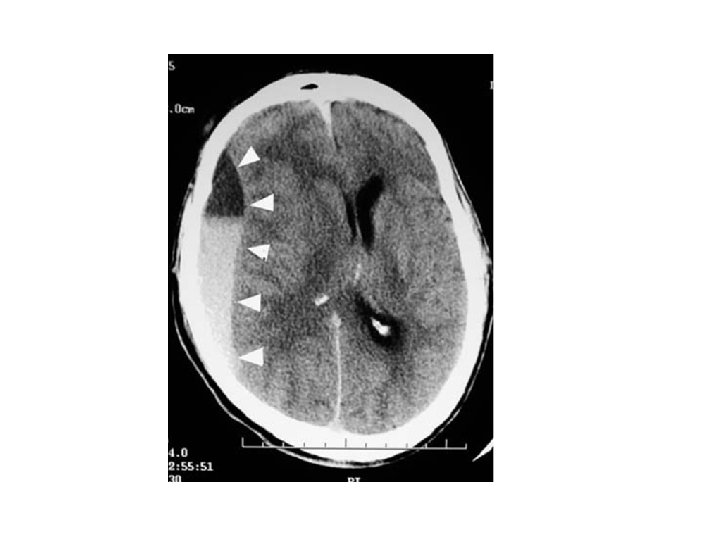

Acute Subdural haematoma • • • Crescentic hyperdense lesion Effacement of the lateral ventricle Midline shift Damage to bridging veins T